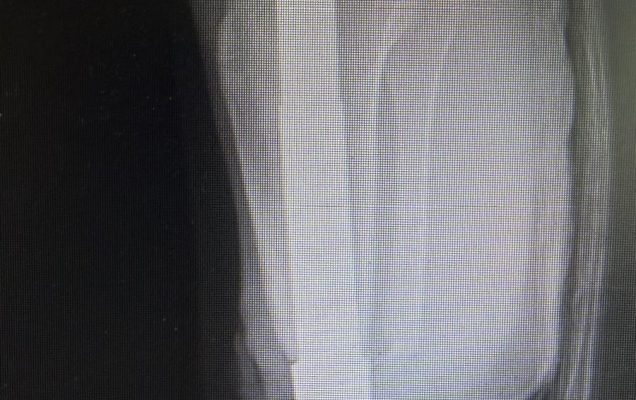

Osseointegracja polega na trwałym połączeniu implantu z kością, co umożliwia bezpośrednie mocowanie protezy bez konieczności stosowania tradycyjnego leja protezowego. Rozwiązanie to zapewnia pacjentom większy komfort użytkowania, lepszą kontrolę ruchu oraz wyraźną poprawę jakości życia. Przeprowadzona operacja była szczególnie wymagająca, ponieważ objęła obie kończyny jednocześnie. Jednoczasowe wykonanie zabiegu niesie jednak istotne korzyści – pozwala uniknąć drugiej hospitalizacji i kolejnego znieczulenia ogólnego, skraca całkowity czas leczenia oraz umożliwia prowadzenie symetrycznej rehabilitacji obu kończyn już od początku procesu usprawniania. Dzięki temu pacjent ma szansę szybciej powrócić do samodzielnego funkcjonowania.

Tego typu zabiegi należą do rzadkości i są wykonywane jedynie w nielicznych, wysoko wyspecjalizowanych ośrodkach. Operacje osseointegracji stanowią ważny krok w kierunku przywracania sprawności i niezależności osobom, które doświadczyły ciężkich urazów.